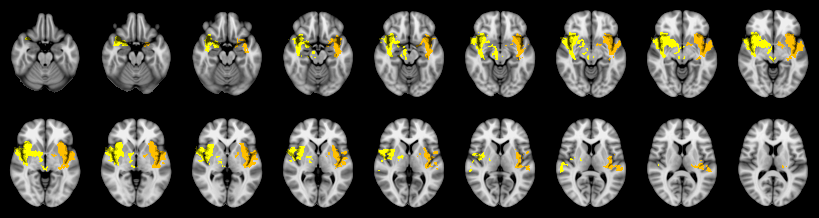

Pain study, Cluster extent, Corrected

Not combined

Combined

Edgington: